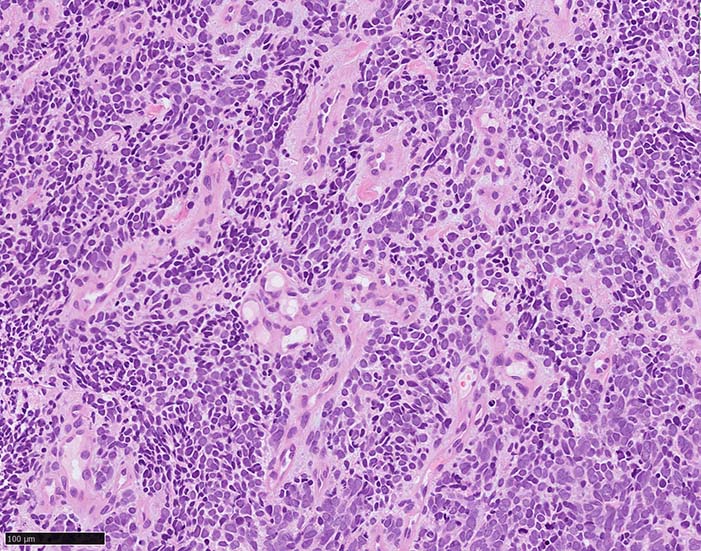

典型的な腫瘍細胞は円形, 卵円形の比較的均一な形態で「salt-and-pepper」と称される微細顆粒状クロマチンを有する小型円形核をもつ. MCPyV陽性例が均一な小型円形核を呈する傾向があり, 陰性例では, 核多形性が目立つととする報告がある.

trabecular type, intermediate type, samll cell typeの3パターンの組織型に分類されているがしばしば混在している.

- trabecular typeは円形から多稜形の腫瘍細胞が索状に配列, 3形のなかで腫瘍細胞がもっとも大きく, 円形核と比較的豊富な細胞質をもつ.

- small cell typeは濃いクロマチン, 多形性を示す核をもつN/C比大の小型腫瘍細胞がびまん性に増殖する.

- intermediate typeではtrabecular, samll cell typeの中間の腫瘍細胞サイズを示す. 組織型としてはもっとも多い.

腫瘍内浸潤リンパ球/炎症細胞は多くの症例で認められる. リンパ球の腫瘍内浸潤は予後良好因子と報告されている. 16

血管を間質にしてround cellsが索状に増殖する所見. rossett様配列がある. CK20は特徴的な dot-like patternを示す. クリックで大きな画像が見られます.